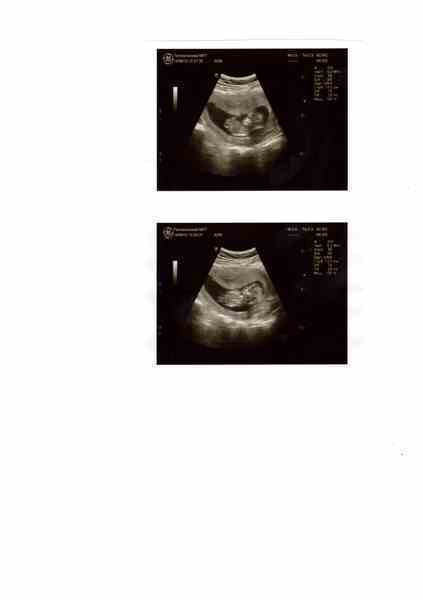

пришла врач, позвала меня. легла я на кушетку, вдохнула и уставилась в монитор)) увидела нашу кошечку) сначала малыш спал и никого не трогал) потом его разбудили! наше солнышко решило поиграть с врачом в прятки)) врач за ним по всему моему пузу гонялся)) а эта красота лежит себе, левая ручка под головой и ножками дрыгает, как лягушонок!! такой лапа)))

а вот наши фото))))